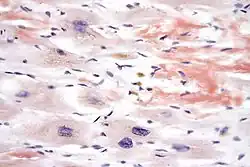

In histology and microscopy, Congo red is used for staining in amyloidosis, and for the cell walls of plants and fungi, and for the outer membrane of Gram-negative bacteria. Apple-green birefringence of Congo red stained preparations under polarized light is indicative of the presence of amyloid fibrils. Additionally, Congo red is used for the diagnostics of the Shigella flexneri serotype 2a, where the dye binds the bacterium's unique lipopolysaccharide structure. Furthermore, Congo red may also be used to induce expression of the type III secretion system of Shigella flexneri, bringing about the secretion of IpaB and IpaC, which form translocation pores within host cell membrane, allowing effector proteins to pass through and alter the host cell's biochemistry. The dye can also be used in flow cytometry experiments for the detection of Acanthamoeba, Naegleria and other amoebal cysts. In confocal microscopy, Congo red can be used as a stable fluorescent stain.[5]